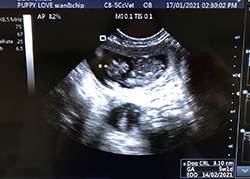

Mobile Ultrasound Pregnancy Scanning and Microchipping Services

Puppy Love scan and chip